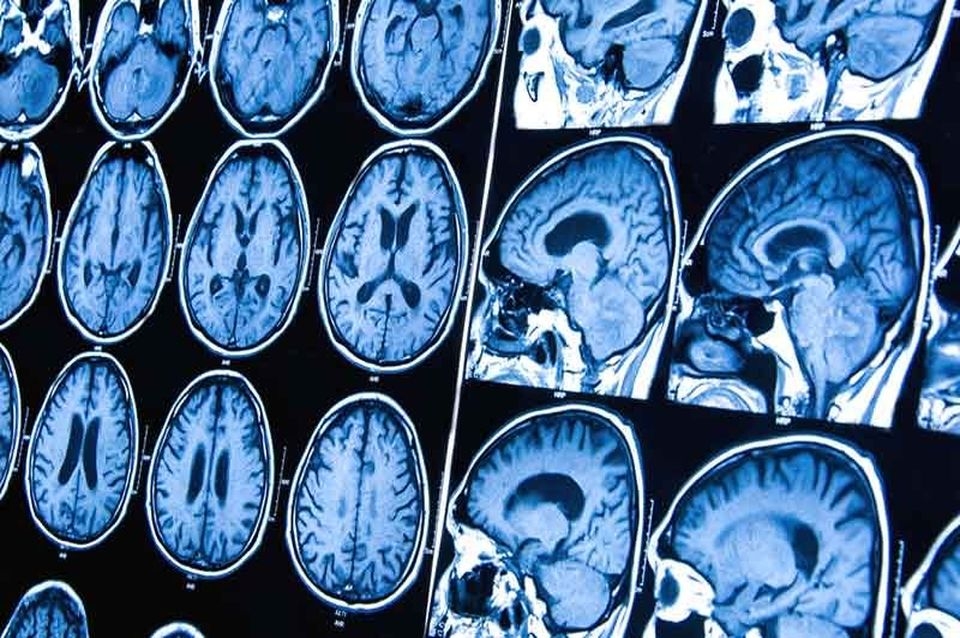

Según la SEOM, el diagnóstico de los tumores cerebrales se realiza mediante la combinación de diferentes pruebas que determinarán la forma, el grado y la extensión del tumor.

El segundo paso son las pruebas radiológicas que permitirán conocer la extensión del tumor, el número de lesiones, tamaño y zonas afectadas. Además, estas pruebas aportarán información relevante, como si el paciente tiene hemorragias, y se utiliza como herramienta complementaria a la valoración de los síntomas. Las pruebas más comunes son el TAC, la resonancia magnética, el PET, el Spect, la punción lumbar y la biopsia.